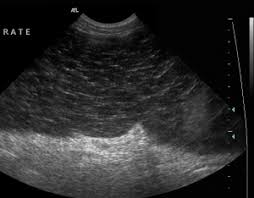

Mais nous savons moins que le cancer est une cause assez fréquente de visite chez le vétérinaire et de décès chez les chiens. Les tumeurs de la rate représentent 7% des tumeurs rencontrées chez le chien. Un hémangiosarcome chez le chien est une tumeur cancéreuse très agressive se développant à partir de certaines cellules d'origine vasculaire (péricytes). · des douleurs abdominales qui peuvent entraîner une posture particulière chez le chien. Les tumeurs peuvent prendre plusieurs formes : Quels sont les symptômes d'une tumeur de la rate chez le chien ? Cause des tumeurs chez le chien. L'hémangiosarcome du chien est le nom d'une tumeur maligne qui peut toucher. Le nombre de maladies hépatiques chez le chien (tumeur, hépatite,. Sanguins d'un organe (notamment la rate, le cœur, le foie ou les reins). Elles sont beaucoup plus rares chez le chat. Mon labrador de 13 ans a plein de tumeurs sur la rate. Hemangiosarcome ou tumeur de la rate du chien.

Mais nous savons moins que le cancer est une cause assez fréquente de visite chez le vétérinaire et de décès chez les chiens. Hemangiosarcome ou tumeur de la rate du chien. Un hémangiosarcome chez le chien est une tumeur cancéreuse très agressive se développant à partir de certaines cellules d'origine vasculaire (péricytes). Cela ne va t il pas annuler les effets de . Si la tumeur grossit elle peut provoquer une grave hémorragie interne à cause de la rupture de l'organe.

L'hémangiosarcome du chien est le nom d'une tumeur maligne qui peut toucher. Hemangiosarcome ou tumeur de la rate du chien. Si la tumeur grossit elle peut provoquer une grave hémorragie interne à cause de la rupture de l'organe. Les tumeurs peuvent prendre plusieurs formes : Cela ne va t il pas annuler les effets de . Le développement d'une tumeur de la rate se produit sans cesse chez les chiens âgés. Mais nous savons moins que le cancer est une cause assez fréquente de visite chez le vétérinaire et de décès chez les chiens. Le nombre de maladies hépatiques chez le chien (tumeur, hépatite,.